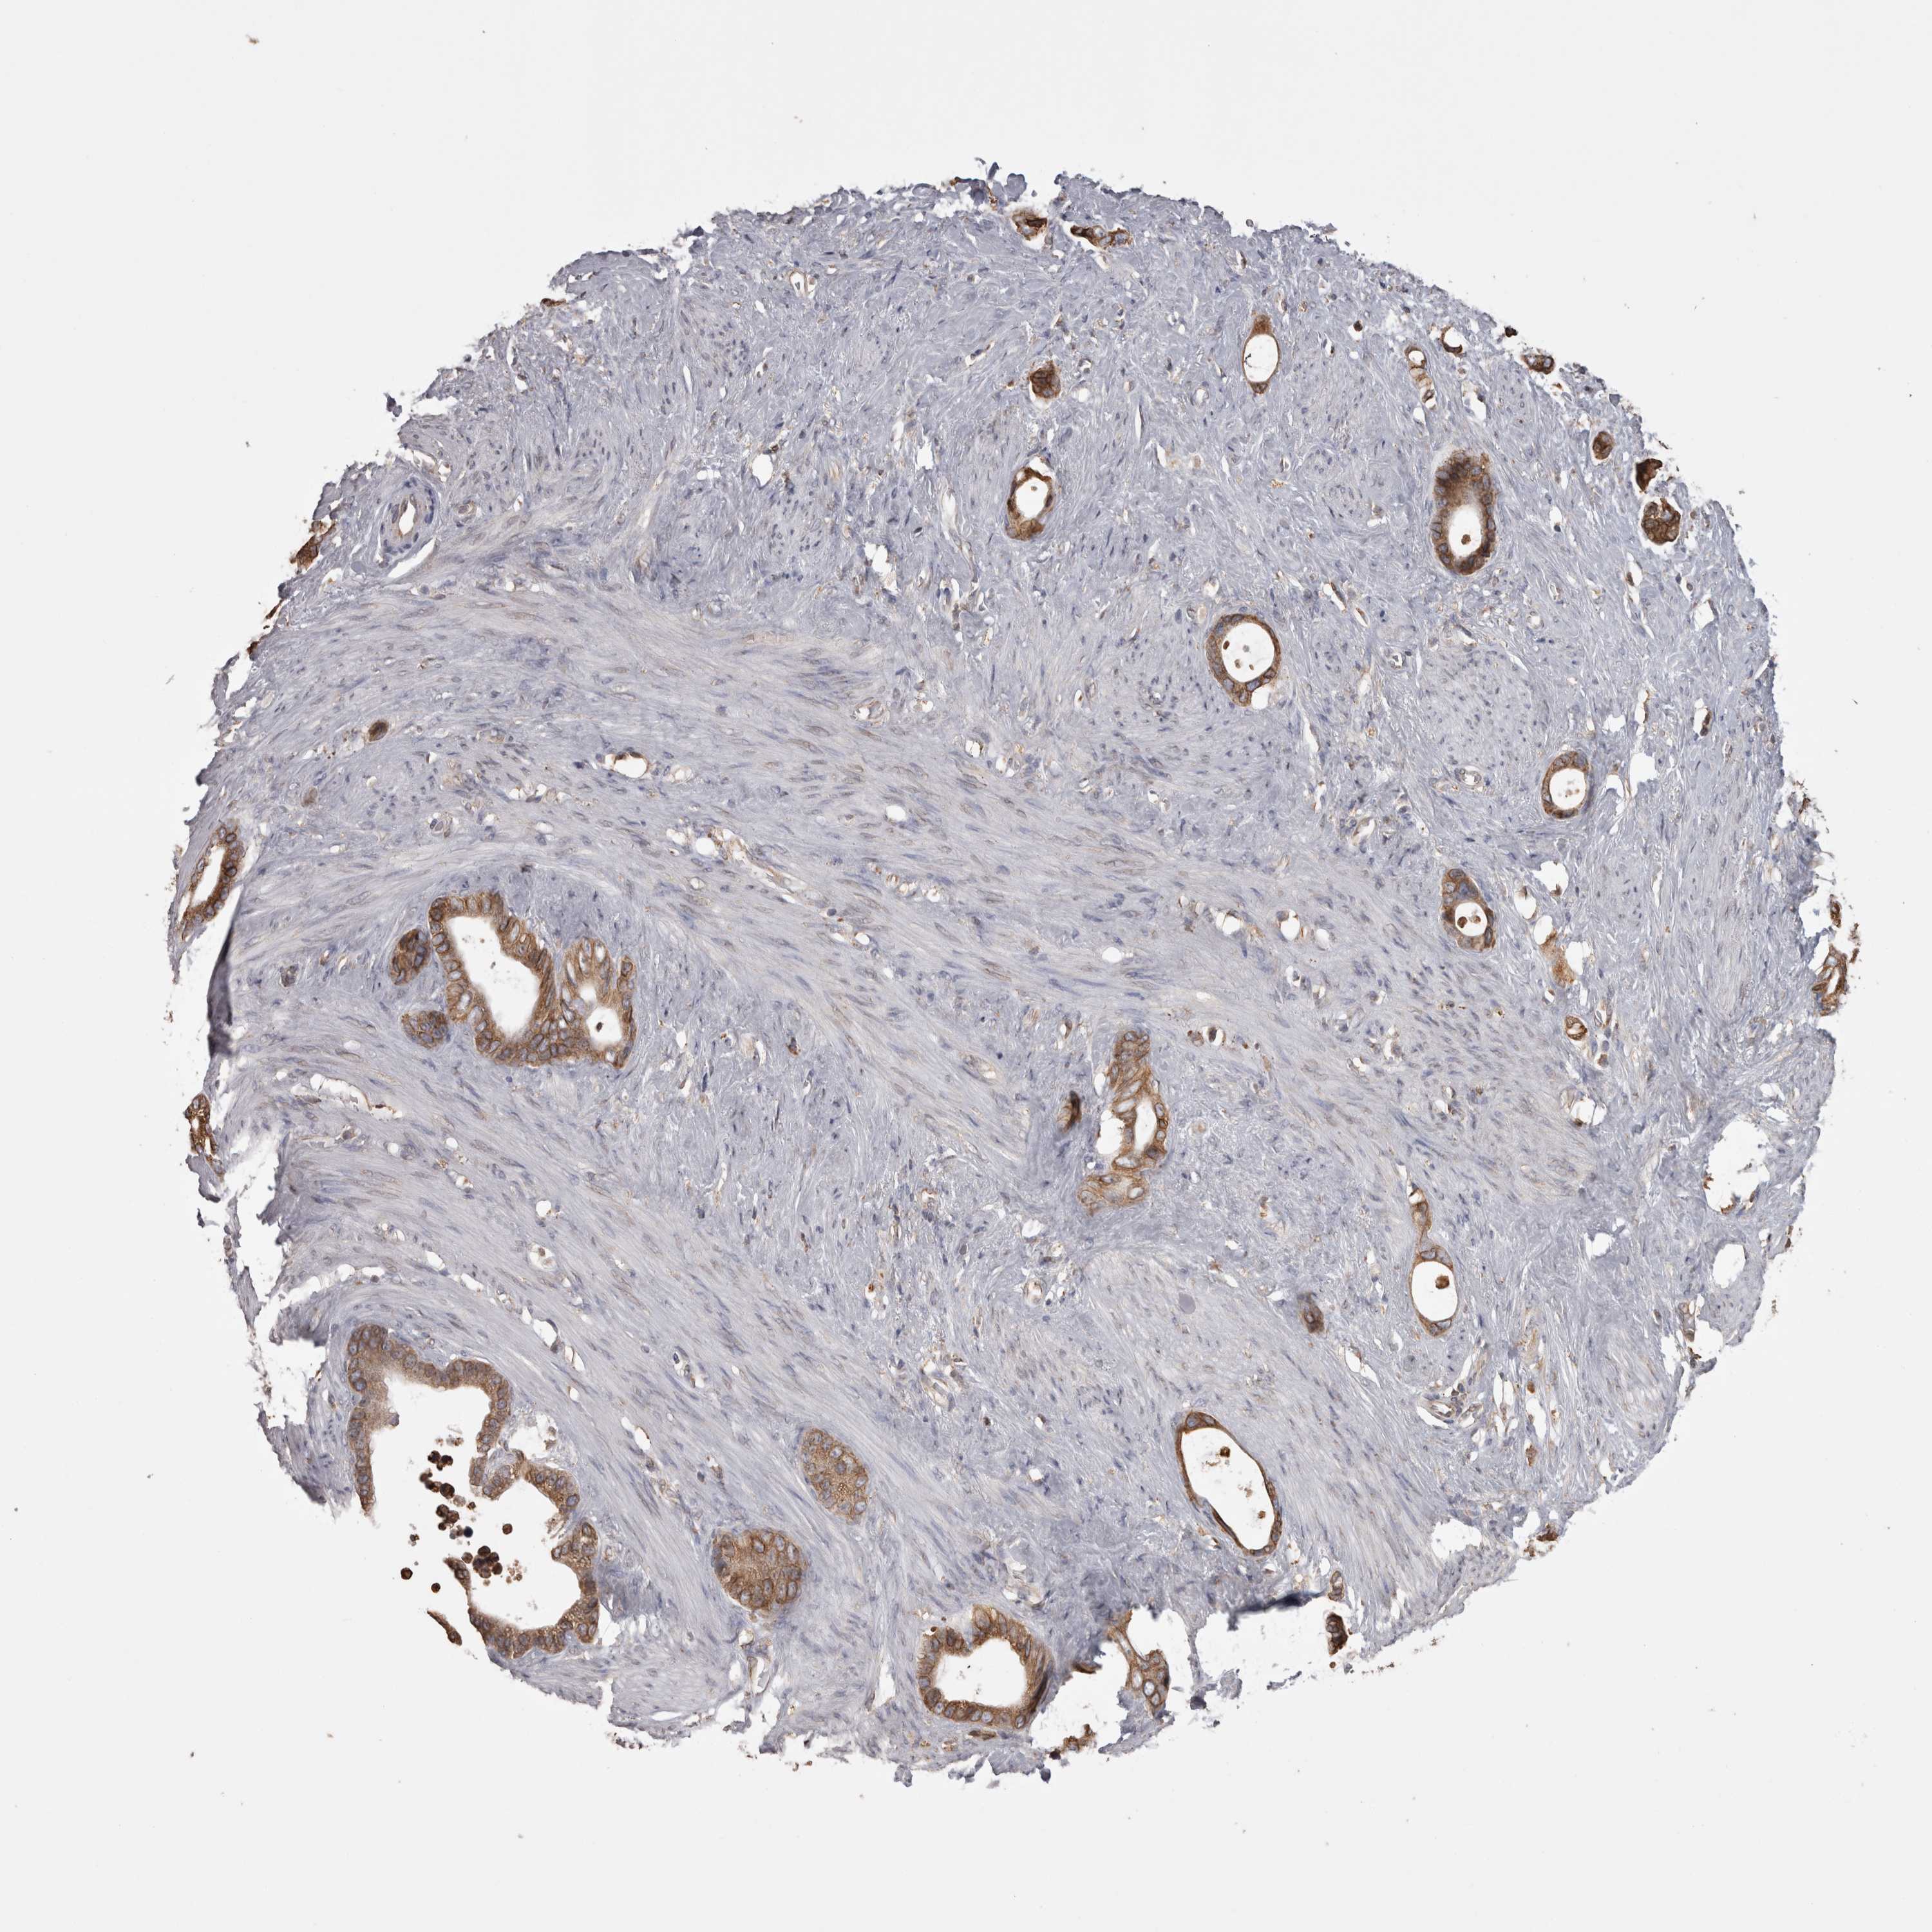

STOMACH CANCER - Protein expressioni

A mouse-over function shows sample information and annotation data. Click on an image to view it in a full screen mode. Samples can be filtered based on level of antibody staining by selecting one or several of the following categories: high, medium, low and not detected. The assay and annotation is described here.

Note that samples used for immunohistochemistry by the Human Protein Atlas do not correspond to samples in the TCGA dataset.

Antibody stainingi

Antibody staining in the annotated cell types in the current human tissue is reported as not detected, low, medium, or high, based on conventional immunohistochemistry profiling in selected tissues. This score is based on the combination of the staining intensity and fraction of stained cells.

Each image is clickable and will lead to virtual microscopy that enables deeper exploration of all samples and also displays staining intensity scores, fraction scores and subcellular localization as well as patient and tissue information for each sample.

Antibody HPA029193

Antibody CAB025430

Staining

High

Medium

Low

Not detected

Intensity

Strong

Moderate

Weak

Negative

Quantity

>75%

75%-25%

<25%

None

Location

Nuclear

Cytoplasmic/membranous

Cytoplasmic/membranous,nuclear

Adenocarcinoma, NOS

Adenocarcinoma, High grade